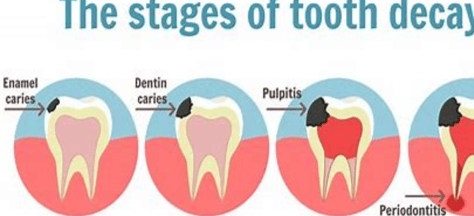

Tooth decay: Tooth decay is a process that causes the breakdown of tooth enamel and dentin. It is caused by a combination of factors, including plaque buildup, sugary foods and drinks, and poor oral hygiene. Tooth decay can cause pain, sensitivity, and tooth loss.

Potential Complications: Untreated tooth decay can lead to tooth death, abscess formation, or systemic infections affecting the heart, brain, or other organs.

These may indicate serious issues like pulpitis or a dental abscess requiring urgent treatment.

These may indicate serious issues like pulpitis or a dental abscess requiring urgent treatment.